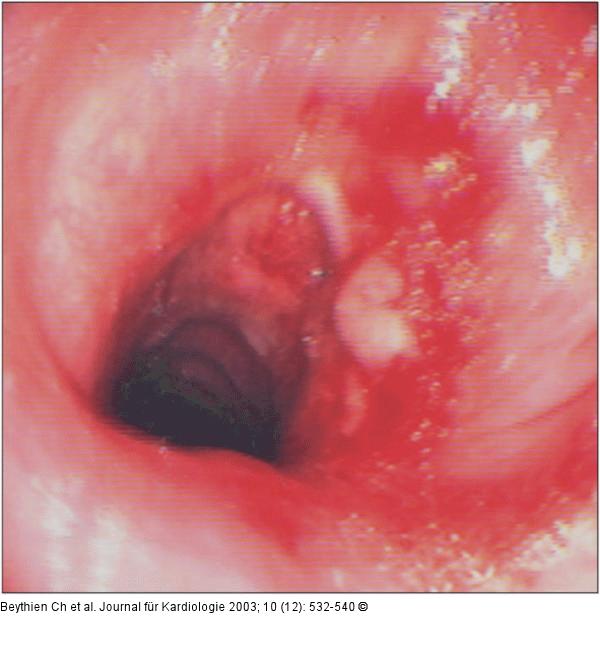

Abbildung 9: Trachea - Stenose - Lasertherapie Verlaufskontrolle 3 Wochen nach Laserabtragung. |